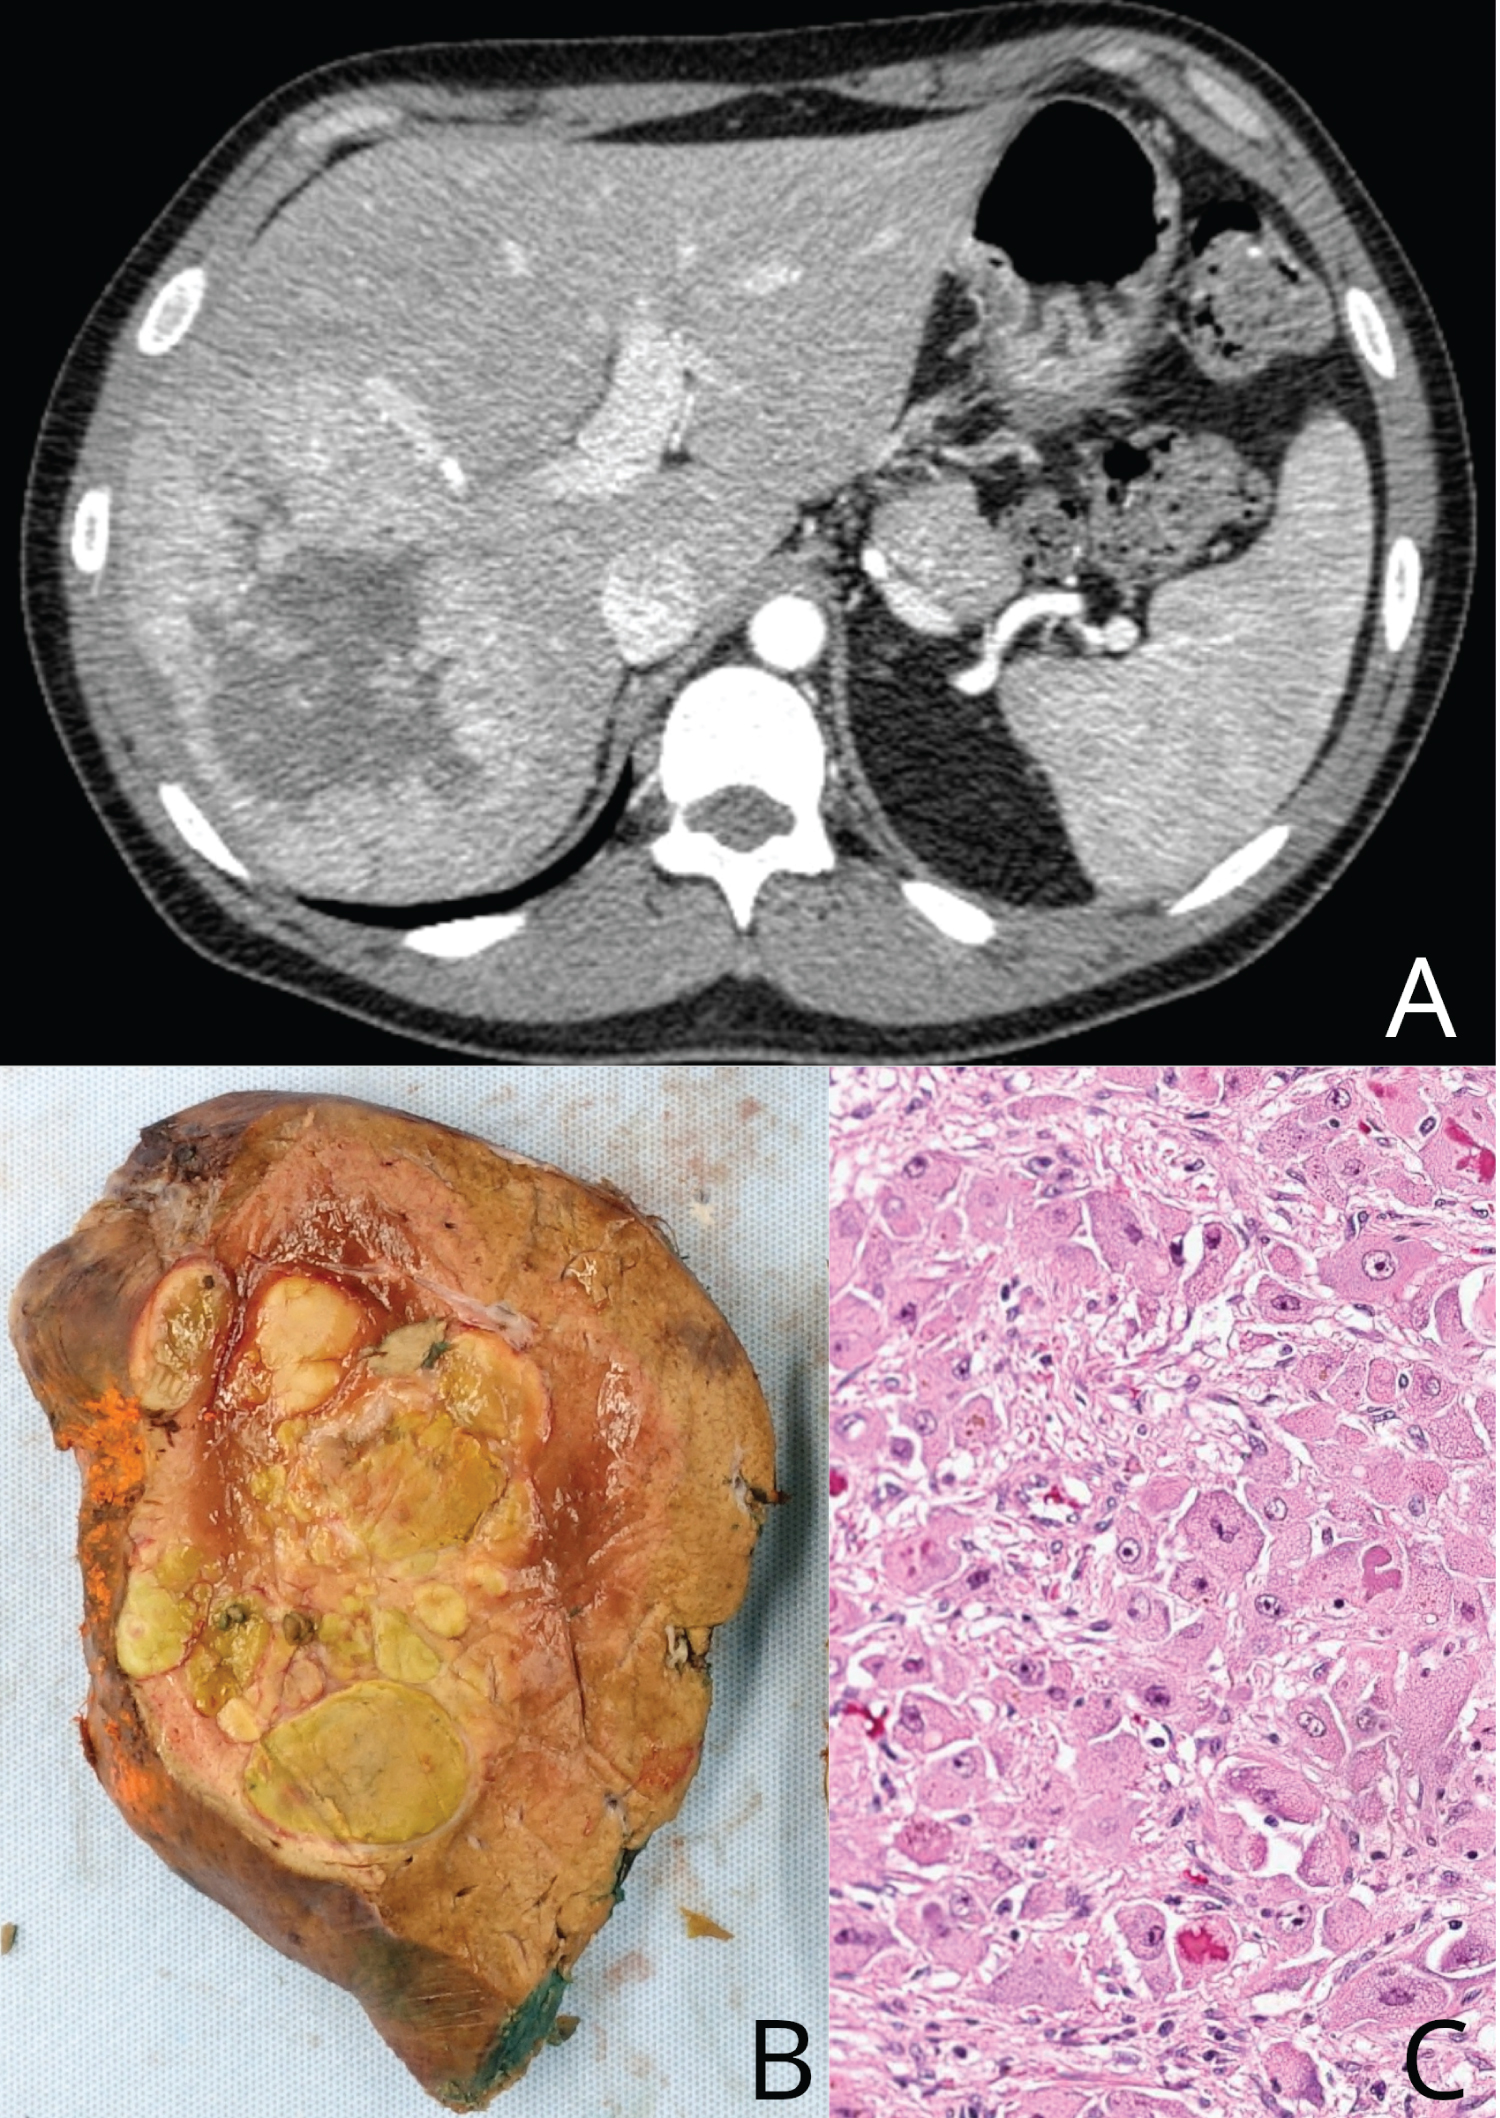

He denied previous alcohol or tobacco use, and his serum alpha fetoprotein level was normal at 3.8 ng/mL. Computed tomography (CT) imaging of his abdomen and pelvis demonstrated a 10.4 cm mass in the right liver with heterogeneous areas of mixed high and low attenuation (Figure 1A).

He underwent right hepatectomy and pathological examination demonstrated a solitary 10.5 × 10.1 × 7.0 cm fibrolamellar hepatocellular carcinoma with negative margins (Figure 1B and Figure 1C).

Figure 1: Liver cancer. (A) Computed tomography (CT) imaging of his abdomen and pelvis demonstrated a 10.4 cm mass in the right liver with heterogeneous areas of mixed high and low attenuation (Panel A); (B and C) Right hepatectomy and pathological examination demonstrated a solitary 10.5 × 10.1 × 7.0 cm fibrolamellar hepatocellular carcinoma with negative margins (Panel B, Panel C).